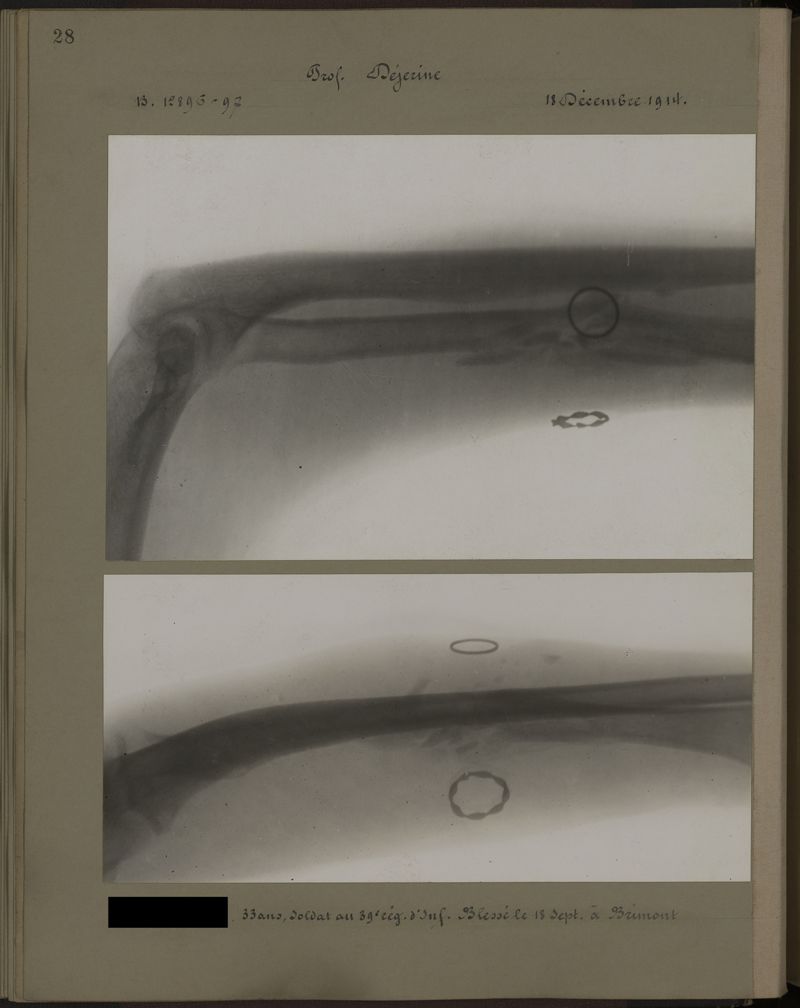

Deux albums de radiographies de la Première Guerre mondiale. Collection du laboratoire central de radiographie de la Salpêtrière. Deuxième album.

1915.